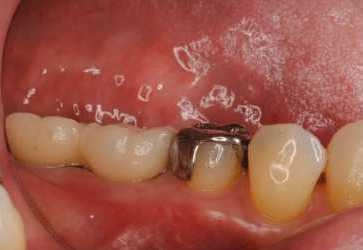

2012.04.28 院長ブログ インプラント3 今日のインプラントは、右下の奥歯に2本でした。本来なら入れ歯になる所ですが、入れなくて済んで良かったと感動されて帰りました。ゴールデンウィークに間に合ってよかったですね。 レントゲンで見るとインプラントから歯に移行する立ち上がりのラインもきれいに仕上がっています。 上の歯が少し伸びてきていて、歯の高さが十分に確保できず上からのネジ固定ですが、ネジ穴もきれいに隠れました。 陶器の色の仕上がりもキレイです。 次の記事 »インプラント2 « 前の記事インプラント矯正